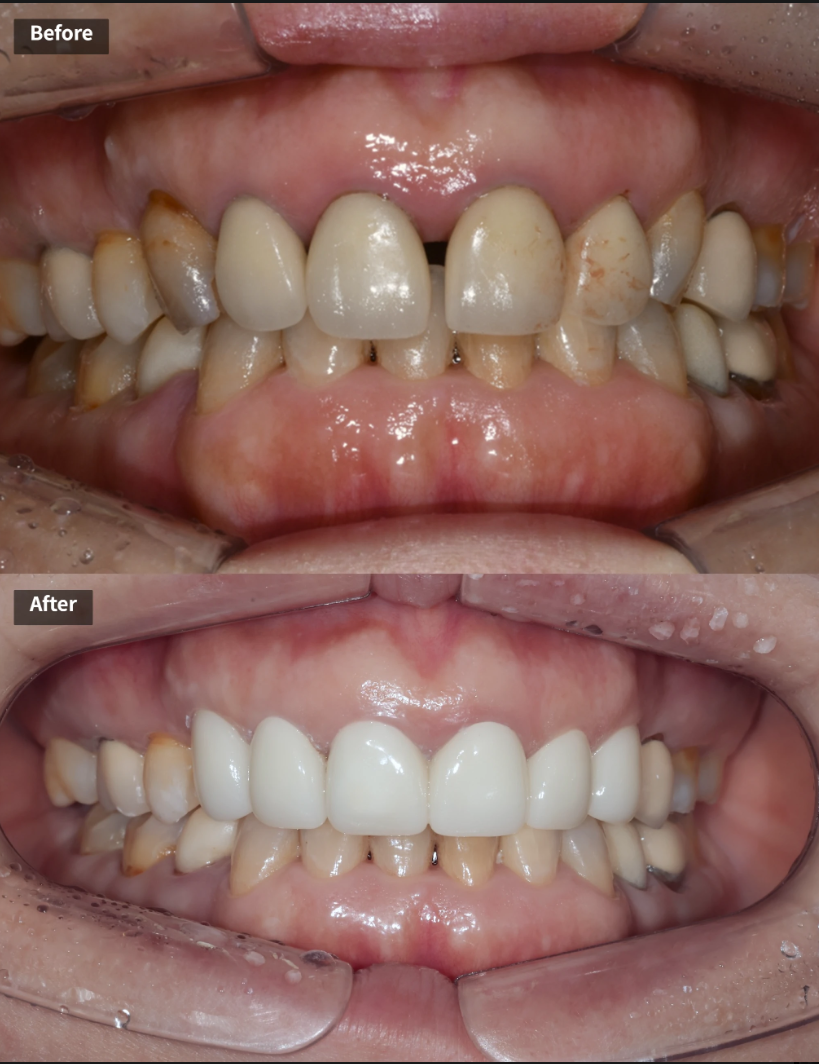

최종 결과 – 자연스럽고 조화로운 앞니 완성

최종 보철 완성 – 모든 치아가 자연스럽게 정리된 모습. 가운데 두 앞니는 연결 크라운으로 제작했습니다

약 3개월간의 임시 크라운 기간을 거친 후, 환자분이 다시 한국에 방문하셨을 때 최종 PFZ 크라운 6개를 세팅했습니다.

치료 전후를 비교하면 다음과 같은 개선이 이루어졌습니다.

| 치료 전 | 치료 후 |

|---|---|

| 치아 사이 검은 삼각형 공간(블랙트라이앵글) | 블랙트라이앵글 대폭 개선 |

| 앞니 사이 벌어진 공간 | 공간 해소, 가지런한 배열 |

| 크라운 변색, 색상 부조화 | 자연스럽고 균일한 색조 |

| 크라운 마진 부적합 | 정밀한 마진 적합 |

| 앞니 사이 다시 벌어질 위험 | 연결 크라운으로 재벌어짐 방지 |

| 입술 돌출 우려 | 평탄한 크라운 윤곽으로 입술 라인 개선 |

아랫니와도 자연스러운 조화를 이루는 모습